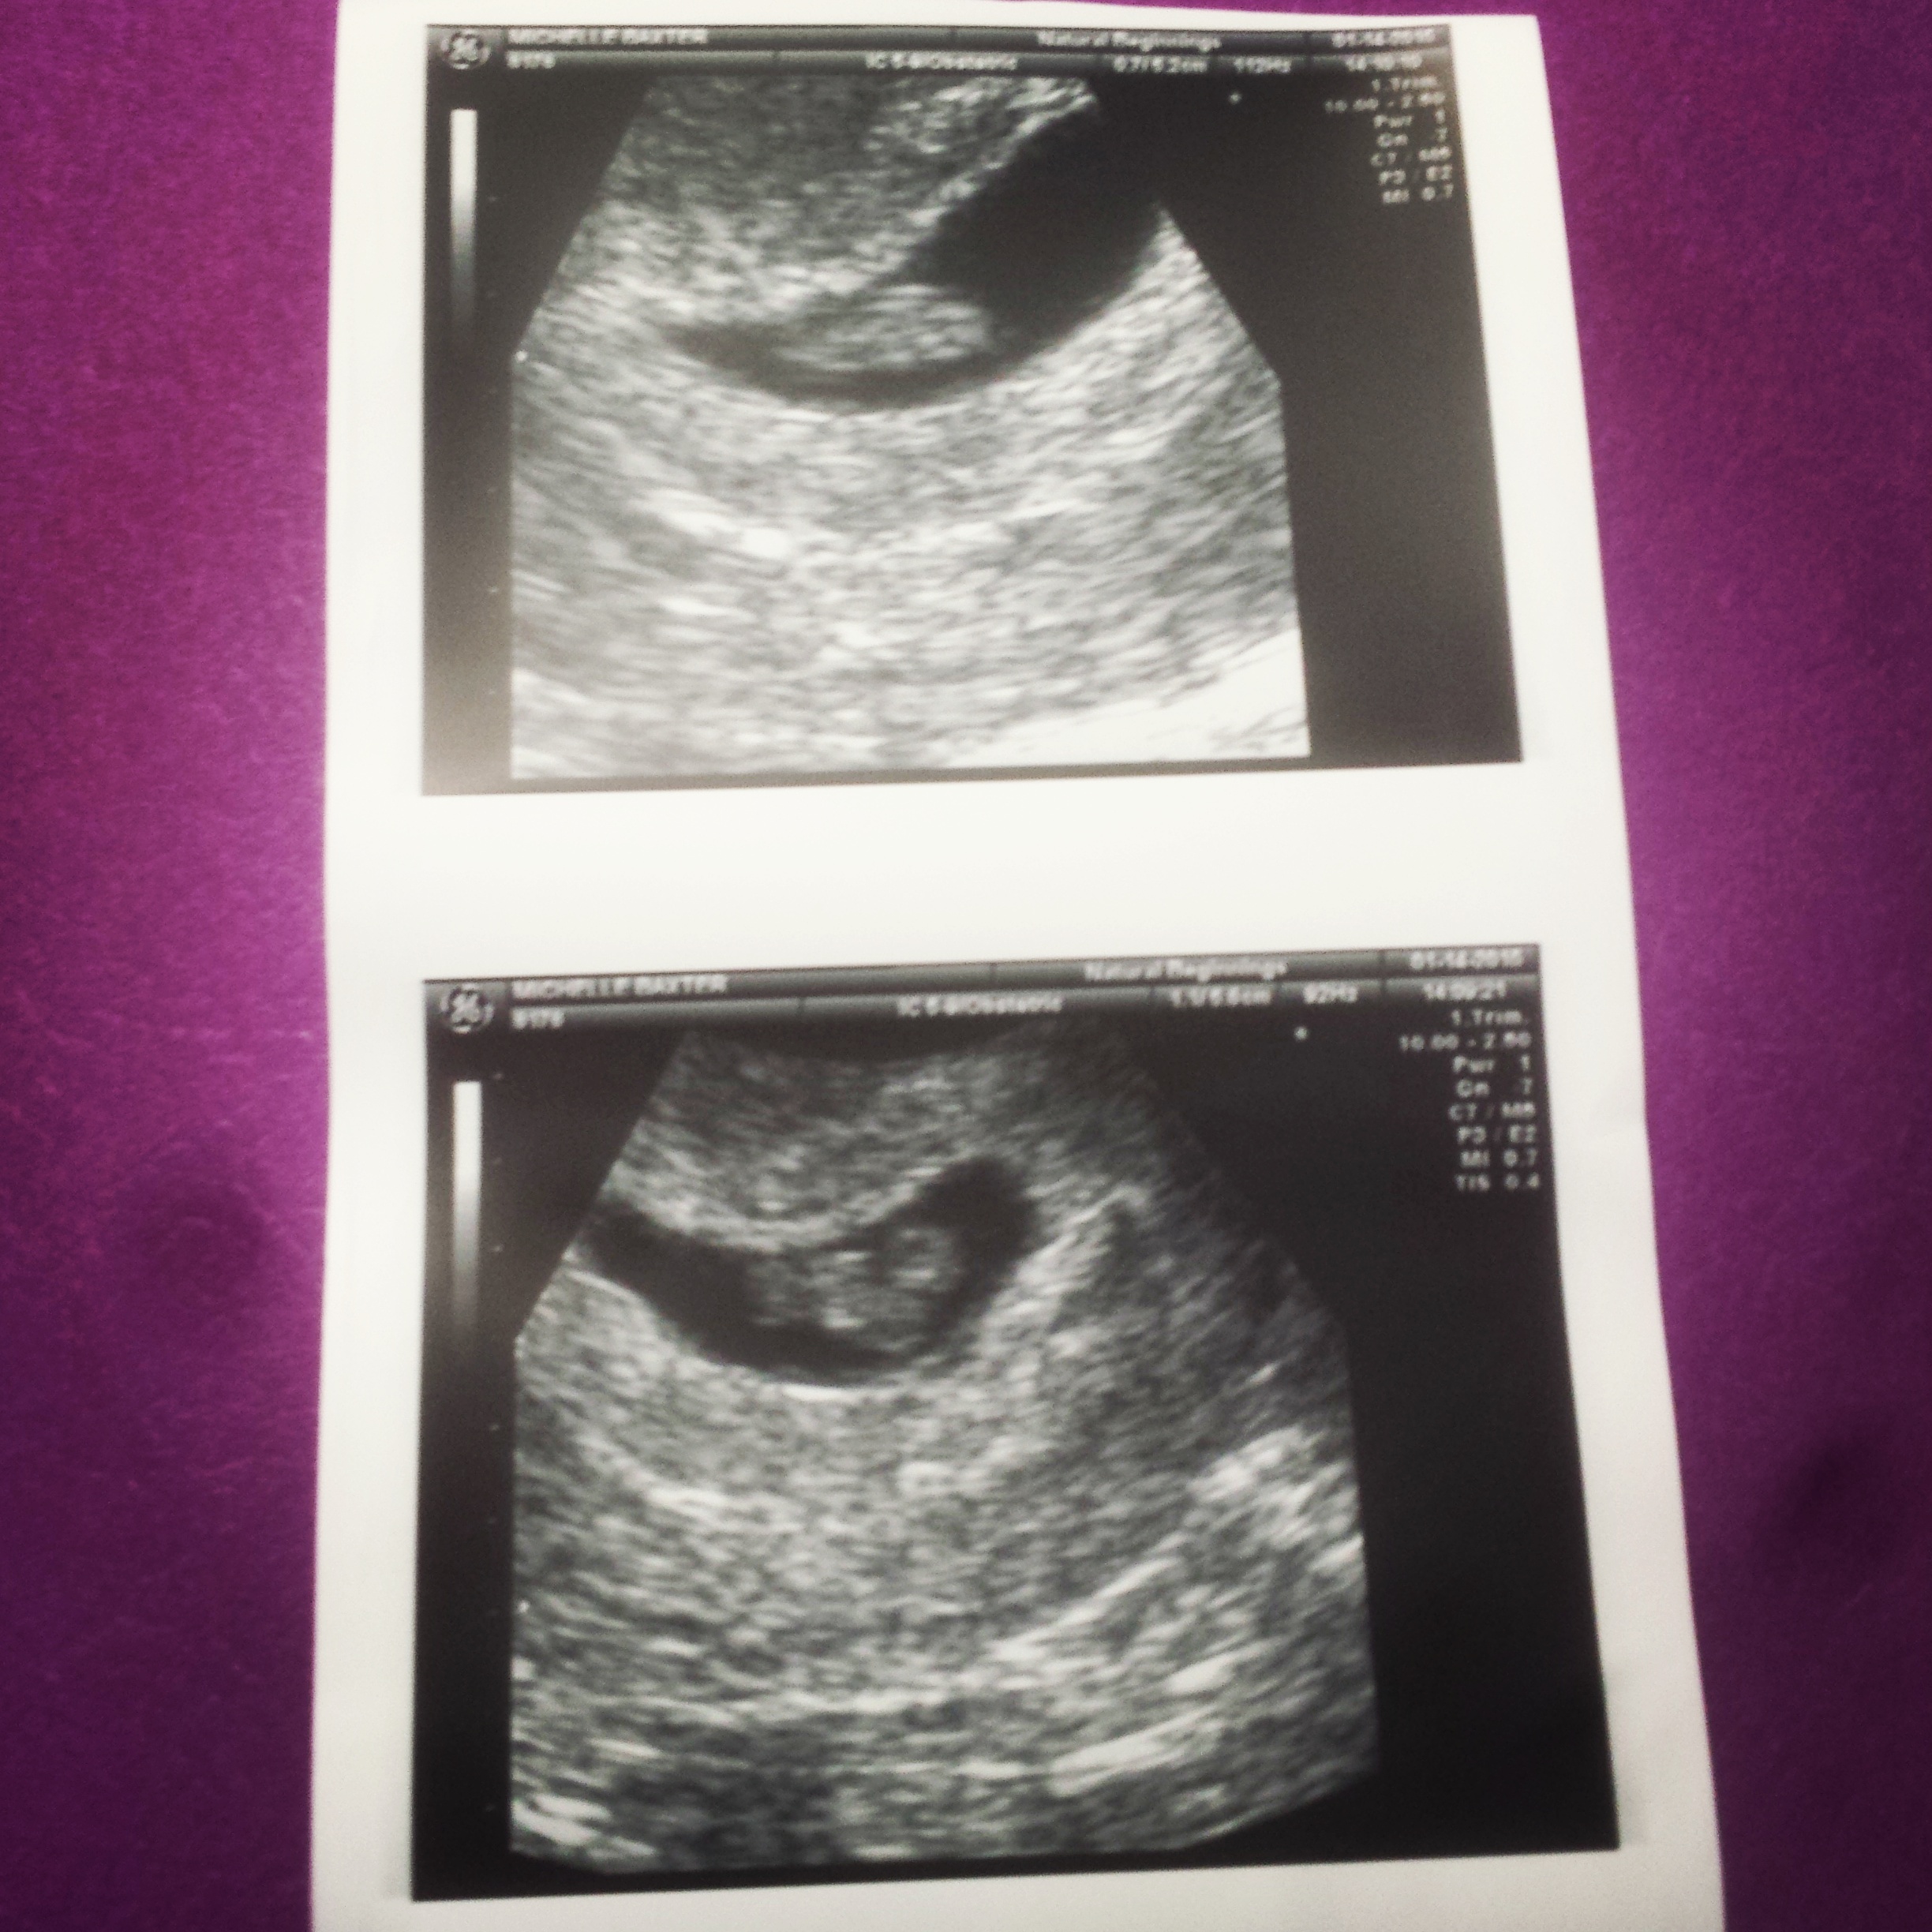

Quick scan done at 11weeks 3 days. FTM. Can't believe how big our baby has gotten from my 7week scan! (There were some concerns so I have gotten a couple of scans)